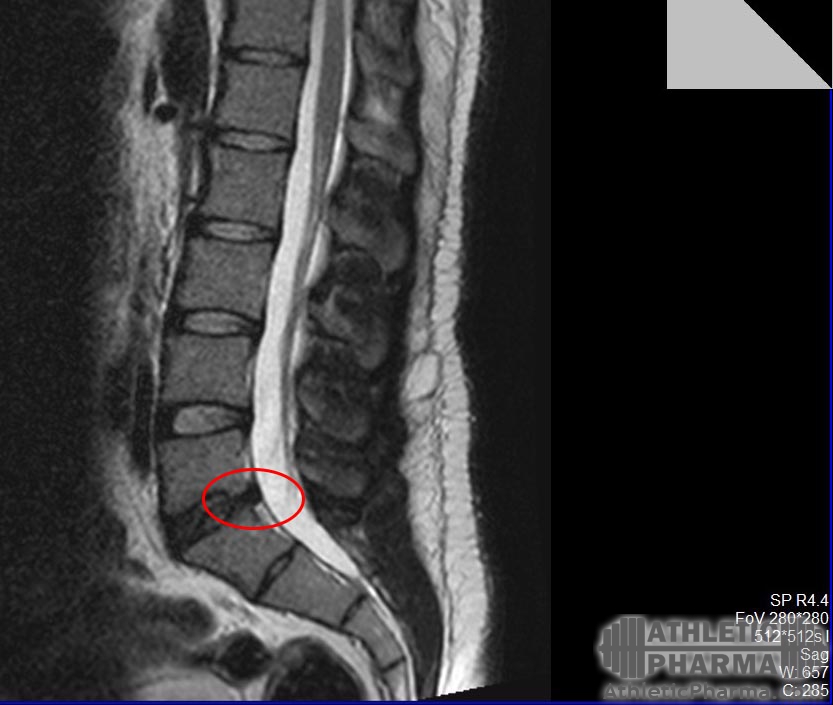

2014 грыжа межпозвоночная